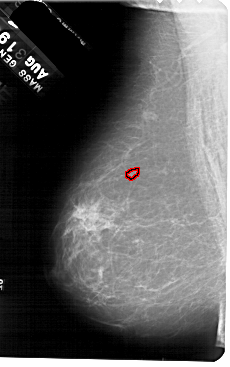

FILE: A_1552_1.LEFT_MLO.OVERLAY

TOTAL_ABNORMALITIES 1

ABNORMALITY 1

LESION_TYPE CALCIFICATION TYPE PLEOMORPHIC DISTRIBUTION CLUSTERED

ASSESSMENT 4

SUBTLETY 2

PATHOLOGY BENIGN

TOTAL_OUTLINES 1

LEFT_MLO LINES 5491 PIXELS_PER_LINE 3436 BITS_PER_PIXEL 12 RESOLUTION 43.5 OVERLAY